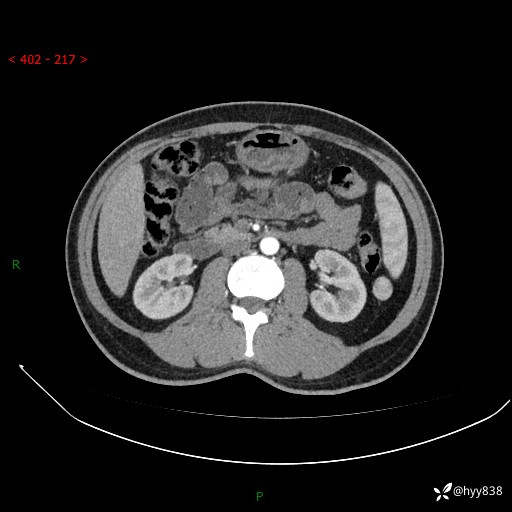

年轻男性,腹痛5月余。除了肠梗阻,你还能看到什么---结果公布~

主诉:腹痛5月余。

现病史:患者于5月前无明显诱因开始出现腹痛,上明显,为间断性胀痛不适,无畏寒发热,无心慌气促等特殊不适,遂来我院。我院门诊遂以“腹痛原因待查”收入我科。 起病以来,患者精神、饮食、睡眠欠佳,大小便正常。体力体重无明显变化。

腹部CT增强扫描(动脉期+静脉期)